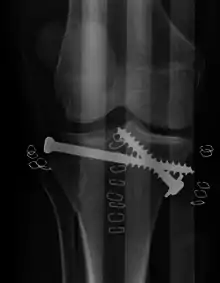

Tratamiento

El tratamiento está enfocado en lograr una articulación estable, alineada, móvil e indolora y en minimizar el riesgo de osteoartritis post-traumática. Para lograr esto, los médicos consideran planes operativos y no-operativos basados en el criterio formado por las características del paciente, la gravedad de la lesión, el riesgo de complicaciones, la depresión y desplazamiento de la fractura, el grado de lesión a los ligamentos y meniscos y el grado de riesgo vascular y neurológico. Para los primeros tratamientos, se debe realizar tracción de manera temprana en la sala. Puede ser tracción cutánea o esquelética. Depende del peso del paciente y de la estabilidad de la articulación. Se introducen tornillos de Schantz sobre el calcáneo y deben ser introducidos del lado medial al lateral. Una vez que la condición sea estable, el plan definitivo deberá reforzar la galvanoplastia y el tornillo de compresión de fijación.